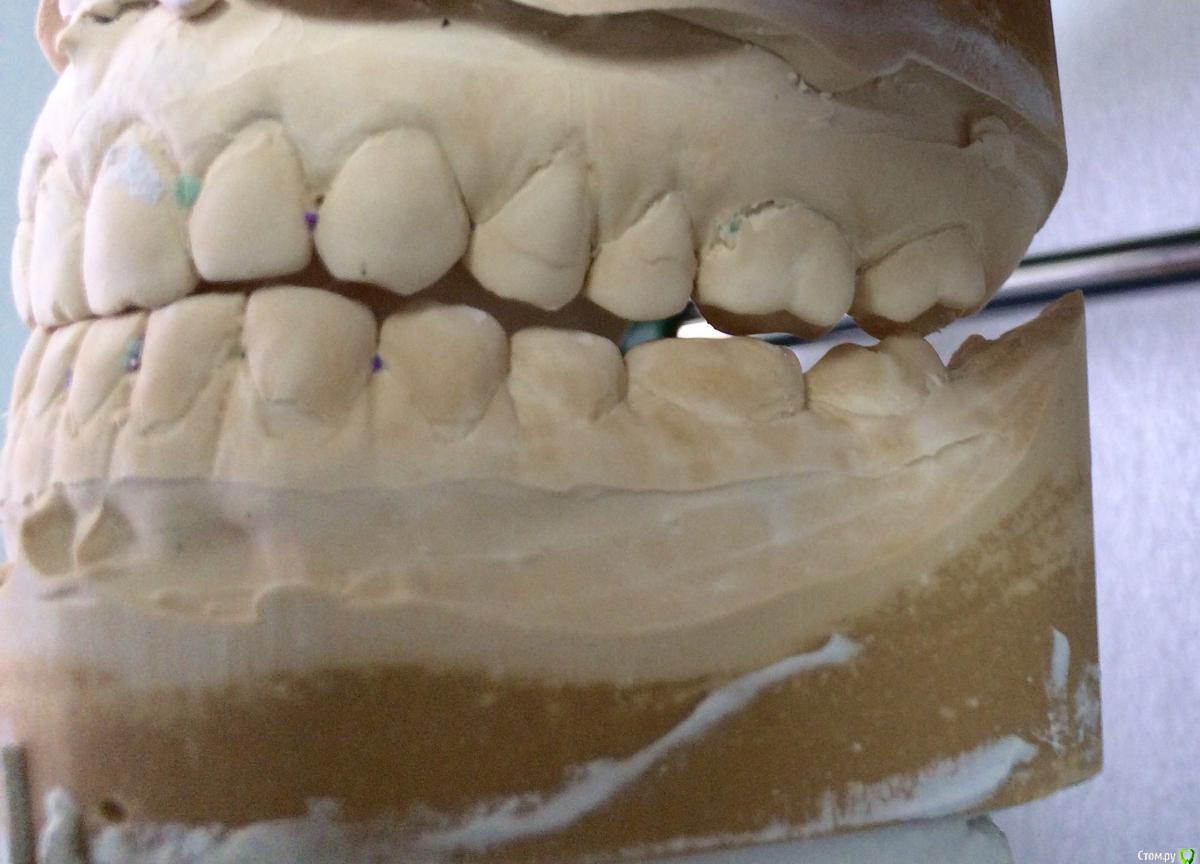

PLAY Опубликовано 28 июля, 2015 Поделиться Опубликовано 28 июля, 2015 Загипсовано в центральном соотношении? Ссылка на комментарий

Larnary Опубликовано 28 июля, 2015 Автор Поделиться Опубликовано 28 июля, 2015 (изменено) в центральной окклюзии Изменено 28 июля, 2015 пользователем Larnary Ссылка на комментарий

Larnary Опубликовано 29 июля, 2015 Автор Поделиться Опубликовано 29 июля, 2015 (изменено) Спасибо огромное за ответ! Модели регистрировал по средним значениям для первичногр анализа. В следуюший прием на следующей неделе буду уже с лицевой дугой регистрировать.А в какой программе Вы делали расчет ТРГ? Изменено 29 июля, 2015 пользователем Larnary Ссылка на комментарий

Skip Опубликовано 3 августа, 2015 Поделиться Опубликовано 3 августа, 2015 Со слов Коиса понял, что в данном случае было бы достаточно создать достаточное функциональное пространство для резцов нижней челюсти, путем брекетов например, вывести передние резцы в/ч в протрузию Не самое лучшее решение при глубоком прикусе. Довольно часто приходится видеть, как попытки решения проблем глубокого прикуса терпят неудачу из-за непонимания принципов передней направляющей. Первое, с чем Вы здесь сразу можете столкнуться, когда будете "выводить резцы в/ч в протрузию", показано на рисунке ниже: http://i11.pixs.ru/storage/4/5/6/09765ukeng_6235790_18261456.jpg Верхние резцы будут наталкиваться на нижнюю губу, из-за чего могут возникнуть проблемы с фонетикой, да и эстетически ничего хорошего. Мало того, полученный результат будет крайне нестабилен вследствие нарушенного нейромышечного равновесия нейтральной зоны, об этом можно почитать у Доусона. Поэтому грамотные ортодонты, зная об этом, проводят не вестибулярный наклон, а интрузию верхних и нижних резцов. Да и говоря в общем, проблема стираемости, при глубоком прикусе, обусловлена не "малым оверджетом", как выразился Александр. Основная проблема состоит в том, что при отсутствии устойчивых удерживающих контактов нижних резцов с верхними в ЦС, происходит их зубоальвеолярная экструзия. Глубокие прикусы, если там решена проблема этих удерживающих контактов на нёбной поверхности коронок верхних резцов , будет среди самых устойчивых видов окклюзии, т.к. с disclusion в боковых отделах здесь почти не бывает проблем. С интерференциями в задних отделах нужно тоже разобраться и делать это нужно в ЦС, перенеся модели в артикулятор с лицевой дугой. На видео можно проследить, к эти интерференции могут стать причиной стираемости передних резцов. http://www.youtube.com/watch?v=2wRffJl82dc http://www.youtube.com/watch?v=My3K-B78iLg 1 Ссылка на комментарий